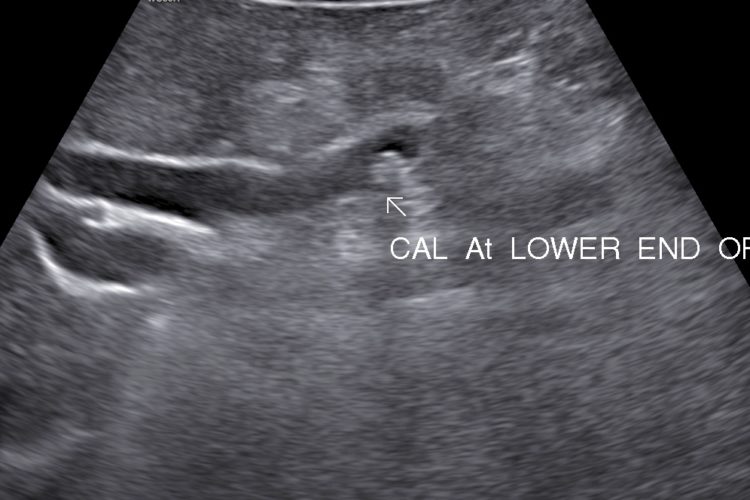

• Choleydocholithiasis (Calculus/ Calculi in Biliary tree): Passage of calculus/caculli in common bile duct leads to biliary colic, nousea, vomitting.

• Surgical jaundice and pancreatitis are complication.